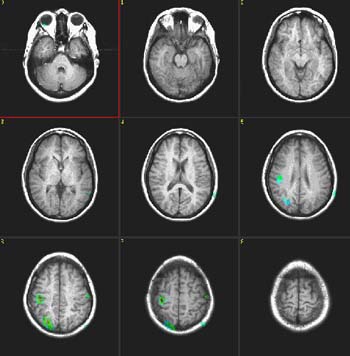

Semantic Fluency

| Subject | Right handed, 25 year-old woman | ||||||

| Paradigm | ON: Retrieving words within a given category OFF: Think of a dark sky | ||||||

| Statistics |

| Activation | The left hemisphere shows predominant activation. The following areas were activated: Broca's, left posterior portion of middle and inferior temporal gyri (Brodman's 37), left parietal and left premotor strip. Wide activation is seen in the inferior aspect of the occipital lobes. The main activation on the right is located in the inferior aspect of the frontal lobe (Brodman's 11), a finding consistently seen in this paradigm. |